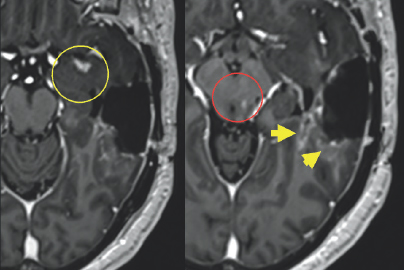

Unfortunately, an MRI scan in October of 2019 revealed worrisome imaging of potential local progression of the tumor (Fig. 2.1–2.3). In addition to this troubling discovery, abnormalities in Columbus’s neuro-cognitive capacity, such as issues with his memory and word-finding capabilities, were gradually becoming more pronounced. This word-finding difficulty showcased itself through his inability to retrieve words for use in regular speech, despite his retention of the ability to understand the English language. To treat these new symptoms, Columbus was put on the steroid dexamethasone.

(Left) Two light gray colored blobs are surrounded by varying dark gray structures. These white blobs have gray spots on them. The first is located in the center of the image and is highlighted by a yellow circle. The other is located towards the right of the image and is highlighted by four small yellow arrows. (Right) A white ribbon-like figure is shown towards the right of the image. It is surrounded by variations of gray color enclosed by a black and white outline.

FIGURE 2.1 Brain MRI before surgery. Axial (left) and coronal (right) post-contrast images show a large mass that appears bright after being injected with IV contrast within the posterior and anterior aspect of the left temporal lobe (yellow arrows and circle), most consistent with high-grade glioma.